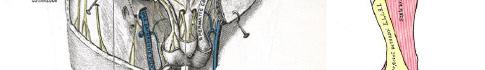

Prior to the start of the procedure, the patient must have IV access and be placed on a cardiac monitor. After informed consent has been obtained, the patient is positioned in the supine position with the head to the contralateral side of the proposed block. The physician stands at the head of the bed above the ipsilateral breast with the ultrasound screen in direct line of sight (commonly at the level of the contralateral hip). The ultrasound probe is initially placed in the sagittal plane at the midclavicular line until the clavicle, pectoralis muscles, and axillary artery and vein are visualized. The transducer is then translated caudally until the third and fourth intercostal spaces are visualized (Image 1).

At this point, the pectoralis major and minor muscles can be visualized. By rotating the transducer 45 degrees clockwise, the thoracoacromial artery can be identified between the pectoralis major and minor muscles. Also, the serratus anterior muscle should be identified resting just above the anechoic rib (Image 2).

Image 1. Initial probe placement for the pectoralis nerve block I and II illustrated on a model: the blue line indicates transducer, and the green dot indicates directional marker corresponding to ultrasound image. Image 2. Final probe placement prior to the pectoralis nerve block I and II: blue line indicates transducer, and green dot indicates directional marker corresponding to ultrasound image.